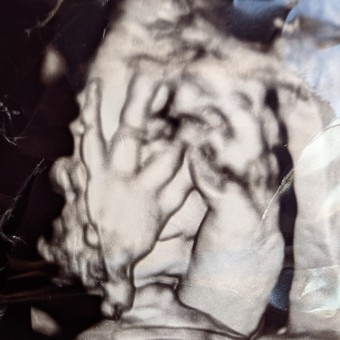

Marina's Baby Registry

Marina Torres

Pasadena, CA

August 2025